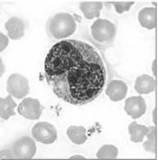

. Neutrófilos (fig3) – São granulócitos (classificação feita com base na presença ou ausência de granulações no citoplasma) com núcleo polilobado e constituem 60% a 70% de todos os leucócitos (3000 a 7000/mm3). Realizam a fagocitose e são os primeiros a chegar aos tecidos infectados, atraídos por quimiotaxia (os basófilos produzem e libertam substâncias capazes de interagir com outros glóbulos brancos do sangue, atraindo-os para o local de libertação desses compostos químicos).

Fig3. Neutrófilo                                                     Fig4. Basófilo